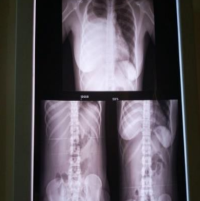

Massive Pulmonary Haemorrhage Presumably Following Surfactant Administration in Very Preterm Neonates in Lagos, Nigeria: Report of Two Cases with Fatal Outcomes and Review of the Literature.

Peter Odion Ubuane, Zainab O. Imam, Ayodeji Olusola Akinola, Omolara Adeolu Kehinde, Ekaete Alaje, Amotunur Lamina, Gbenga Akinyosoye, Bridget Fagbuji, Oluwabukola Jeje, Elizabeth Aruma Disu, Fidelis Olisamedua Njokanma (Author)

36-41